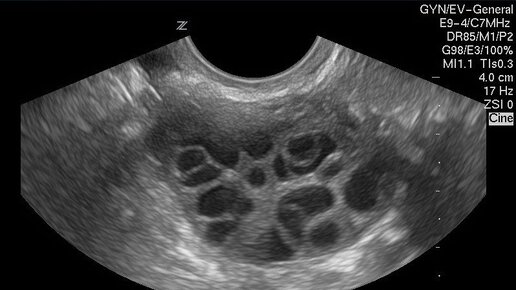

Поликистоз почек — это серьезное наследственное заболевание, которое характеризуется образованием множества кист в тканях почек. Эти кисты представляют собой полости, заполненные жидкостью, и могут влиять на нормальное функционирование почек. Важно отметить, что единичные кисты, возникающие в почках, обычно не вызывают проблем и не требуют лечения. Однако поликистозные изменения могут привести к почечной недостаточности, что делает это заболевание опасным. Поликистоз почек, или поликистозная болезнь почек (ПКБ), — это заболевание, при котором в обеих почках образуется множество кист...